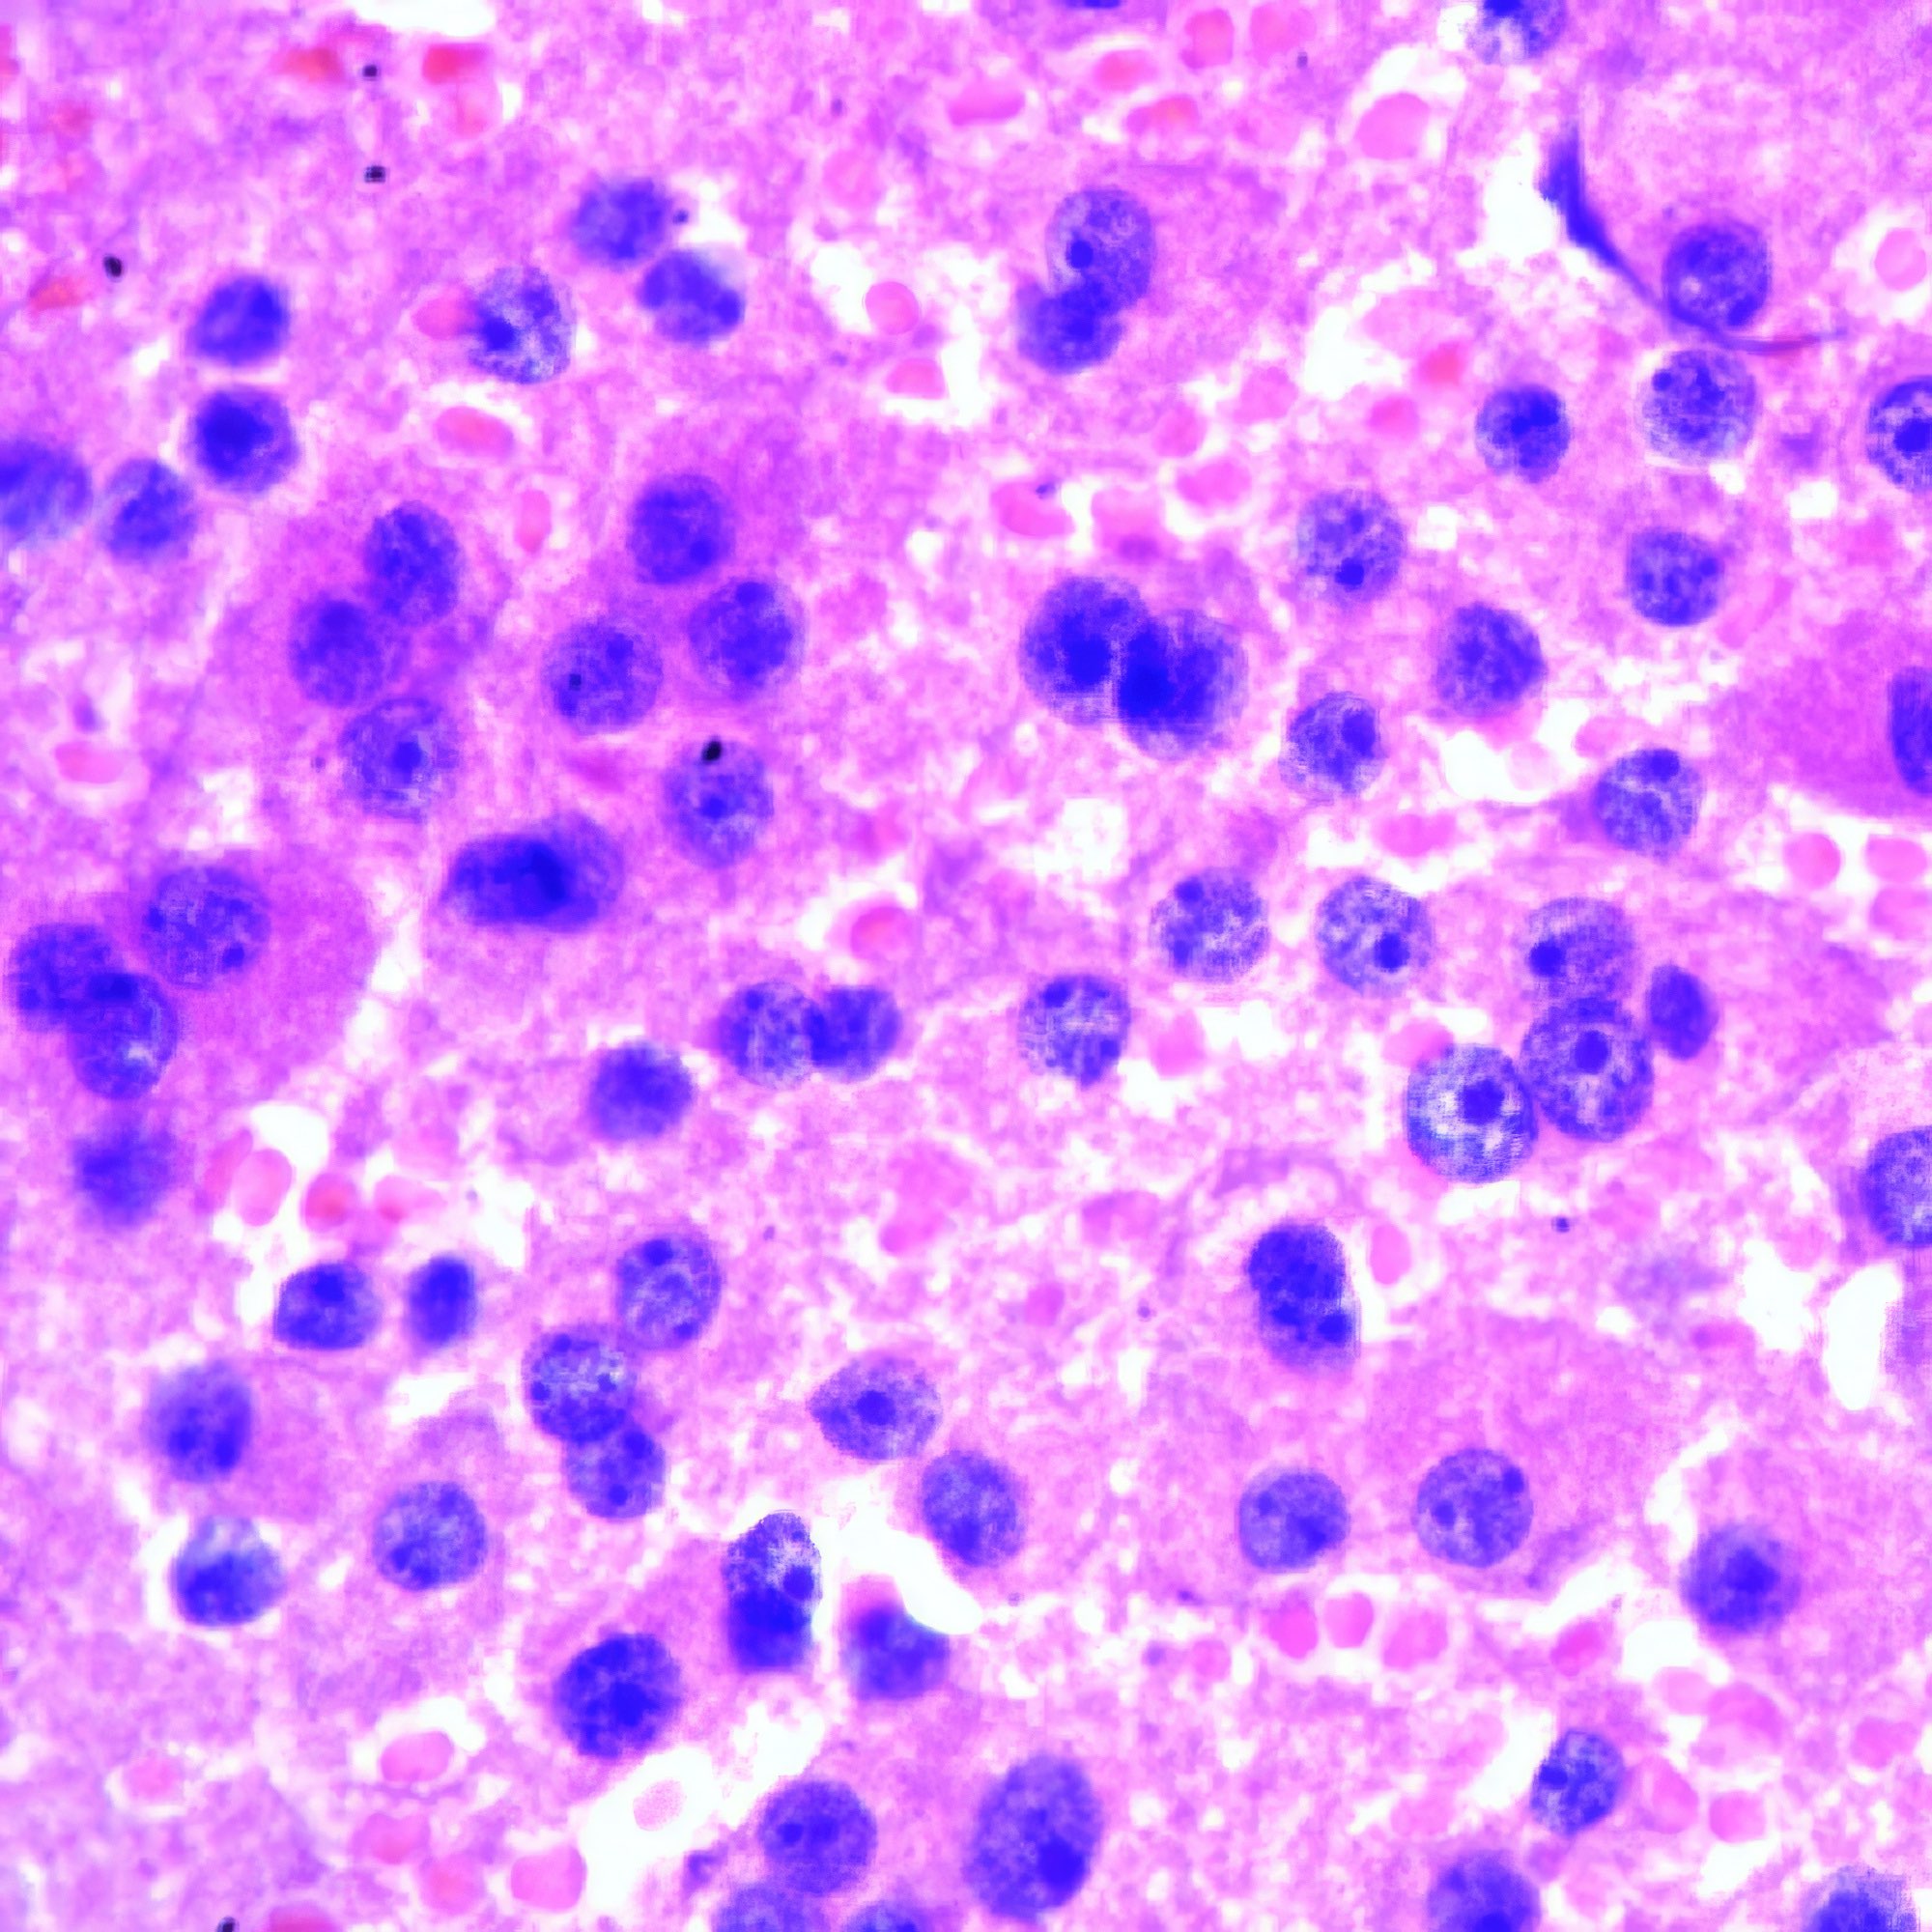

M, 8 Jahre alt, beidseitige Schwellung der Halslymphknoten, weiße Blutzellen 110’000, Lym 43.8%, Gran 23.5%, RBC 2.46, HB 8g/dl, PLT 30 000, CRP 96.

Akute lymphatische Leukämie (ALL)

Die Bilder der Lymphknoten-FNA zeigen außer Blut nur kleine lymphozytäre, keine größeren follikuläre Zellen, wie bei einem Patienten in so jungem Alter zu erwarten. Die kleinen Zellen variieren erheblich in der Form und wenig in der Größe; einzelne von ihnen sind hantelförmig. Vereinzelt geschrumpfte strukturlose pyknotische Kerne (Abb. a li. oben). Die vitalen Zellen zeigen jedoch eine mehr oder weniger normale klumpige Chromatinstruktur (Abb. a, b). Infolge der Trocknung vor der Fixierung erscheinen die Giemsa-gefärbten Zellen im Blutausstrich viel größer, aber auch deutlicher polymorph (Abb. c, d).

Bis vor einigen Jahren wurde die FNA ausschließlich bei erwachsenen Patienten und nur selten bei Kindern angewendet {1}. Im vorliegenden Fall zeigen die ausgezeichneten Bilder, dass das Ergebnis von der Erfahrung des Arztes abhängt, der sie anwendet. Die durch die Pap-Färbung gut sichtbare Chromatinstruktur macht zusätzliche Tests zur Abgrenzung von anderen kleinzelligen Tumoren wie Ewing-Sarkom, Neuroblastom und Wilms-Tumor überflüssig. Die zytologische Diagnose wird durch die klinischen Daten gestützt. Die für die ALL typische Knochenmarksbeteiligung lässt sich an den klinischen Daten ablesen, d.h. an der niedrigen Zahl der roten Blutkörperchen (RBC) und der Blutplättchen sowie dem niedrigen Hämoglobinspiegel (HB). Etwa 80 % der ALL sind vom B-Zell-Typ. Ihre Entwicklung scheint von angeborenen DNA-Veränderungen abzuhängen. Wie in einer neueren Arbeit gezeigt wurde, sind Kinder mit Trisomie 21, der genetischen Ursache des Down-Syndroms, mit einem 20-fach erhöhten Risiko für ALL assoziiert {2}. Im Gegensatz zur ALL tritt die akute myeloische Leukämie (AML) nicht vor der Adoleszenz auf.